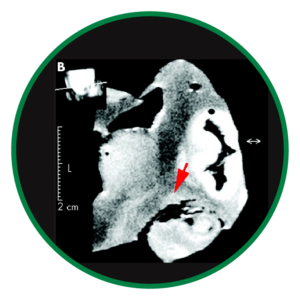

La neurodegeneración glaucomatosa se extiende más allá del nervio óptico, afectando estructuras cerebrales clave como el núcleo geniculado lateral y la corteza visual. Estudios de neuroimagen han demostrado atrofia y alteraciones funcionales en estas áreas, lo que confirma que el glaucoma implica un compromiso del procesamiento visual central.2

La resonancia magnética muestra cambios estructurales y reducción del tamaño del núcleo geniculado lateral en el glaucoma frente a controles.2